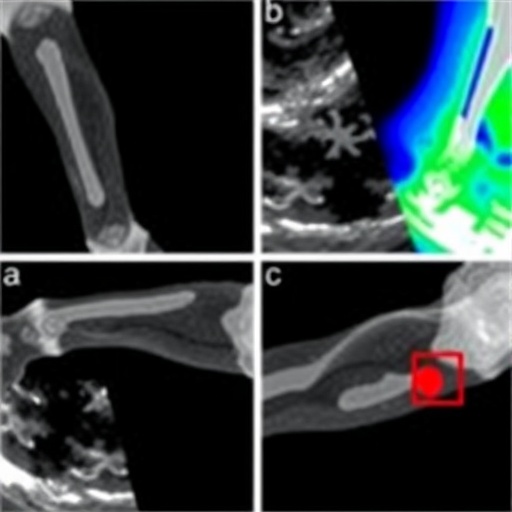

One of the central tenets of their research lies in the description of sonographic features indicative of an irreducible pulled elbow. The paper outlines several specific findings that radiologists and medical professionals should look for, including alterations in the position of the radial head and changes in the surrounding soft tissue structures. With specialized training in these techniques, practitioners can gain a better understanding of the nuances involved in diagnosing this condition accurately. The authors meticulously detail these aspects, ensuring that the guidelines provided are not only actionable but also scientifically sound.

Moreover, the review performs an in-depth analysis of the available studies on the accuracy of sonographic assessments for diagnosing this injury. Key data drawn from various research projects lend credence to the proposal that ultrasound is not merely a supplemental tool but could serve as a definitive diagnostic technique. The statistical outcomes shared within the review reflect a high level of sensitivity and specificity, bolstering the claim that incorporating ultrasound into the assessment of potential pulled elbow cases could streamline and improve patient care.